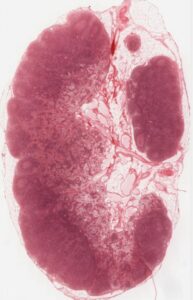

Figure 21.10 Locations and Histology of the Tonsils (a) The pharyngeal tonsil is located on the roof of the posterior superior wall of the nasopharynx. The palatine tonsils lay on each side of the pharynx. (b) A micrograph shows the palatine tonsil tissue. LM × 40. (Micrograph provided by the Regents of the University of Michigan Medical School © 2012) (OpenStax)

Figure 21.11 Mucosa-associated Lymphoid Tissue (MALT) Nodule LM × 40. (Micrograph provided by the Regents of the University of Michigan Medical School © 2012) (OpenStax)